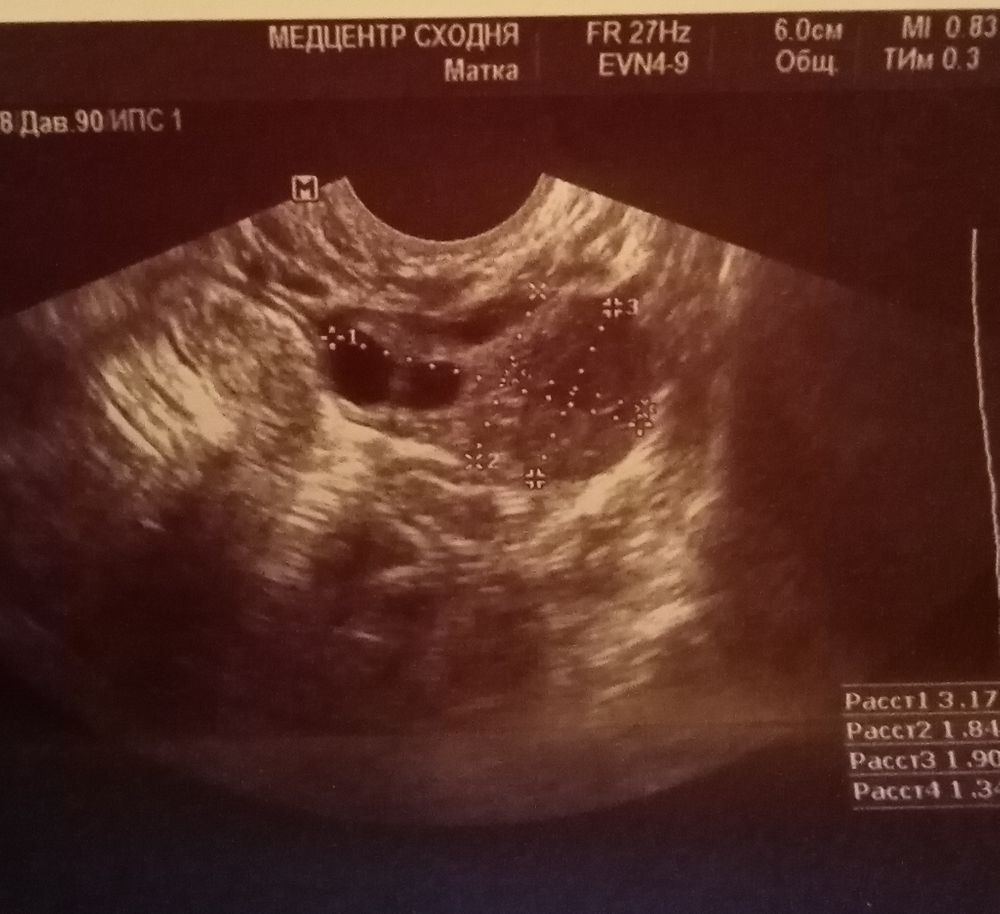

Эх, девушки, по-ходу, я поймала 2ую О🤷♀️На 11дц на узи есть жт и жидкость,западение бт, но клеар -😑13дц-клеар +, полоска поярчала🤔14дц-бт упала, клеар опять + и тестовая полоска сравнялась🙏В позапрошлом цикле при такой же яркости полоски по УЗИ поставили О в тот же день☺️Возможна ли сегодня 2ая О?🤞

Бусинка, на 1ом фото справа жт, а слева, чёрные круги, фолики🤷♀️у другого Г консультировалась и ей фотки отправляла